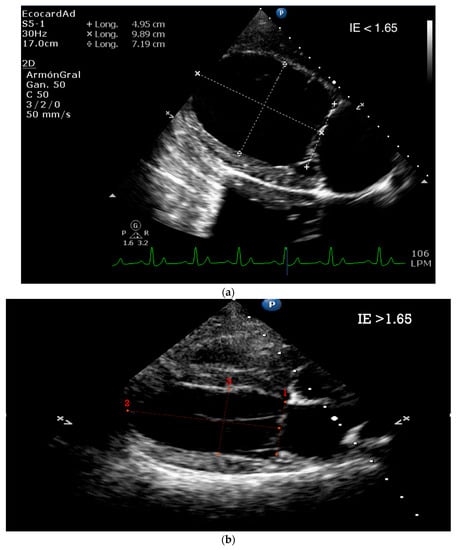

5.1.3. Sphericity Index (SI)

5.1.4. Tissue Doppler and Speckle Tracking